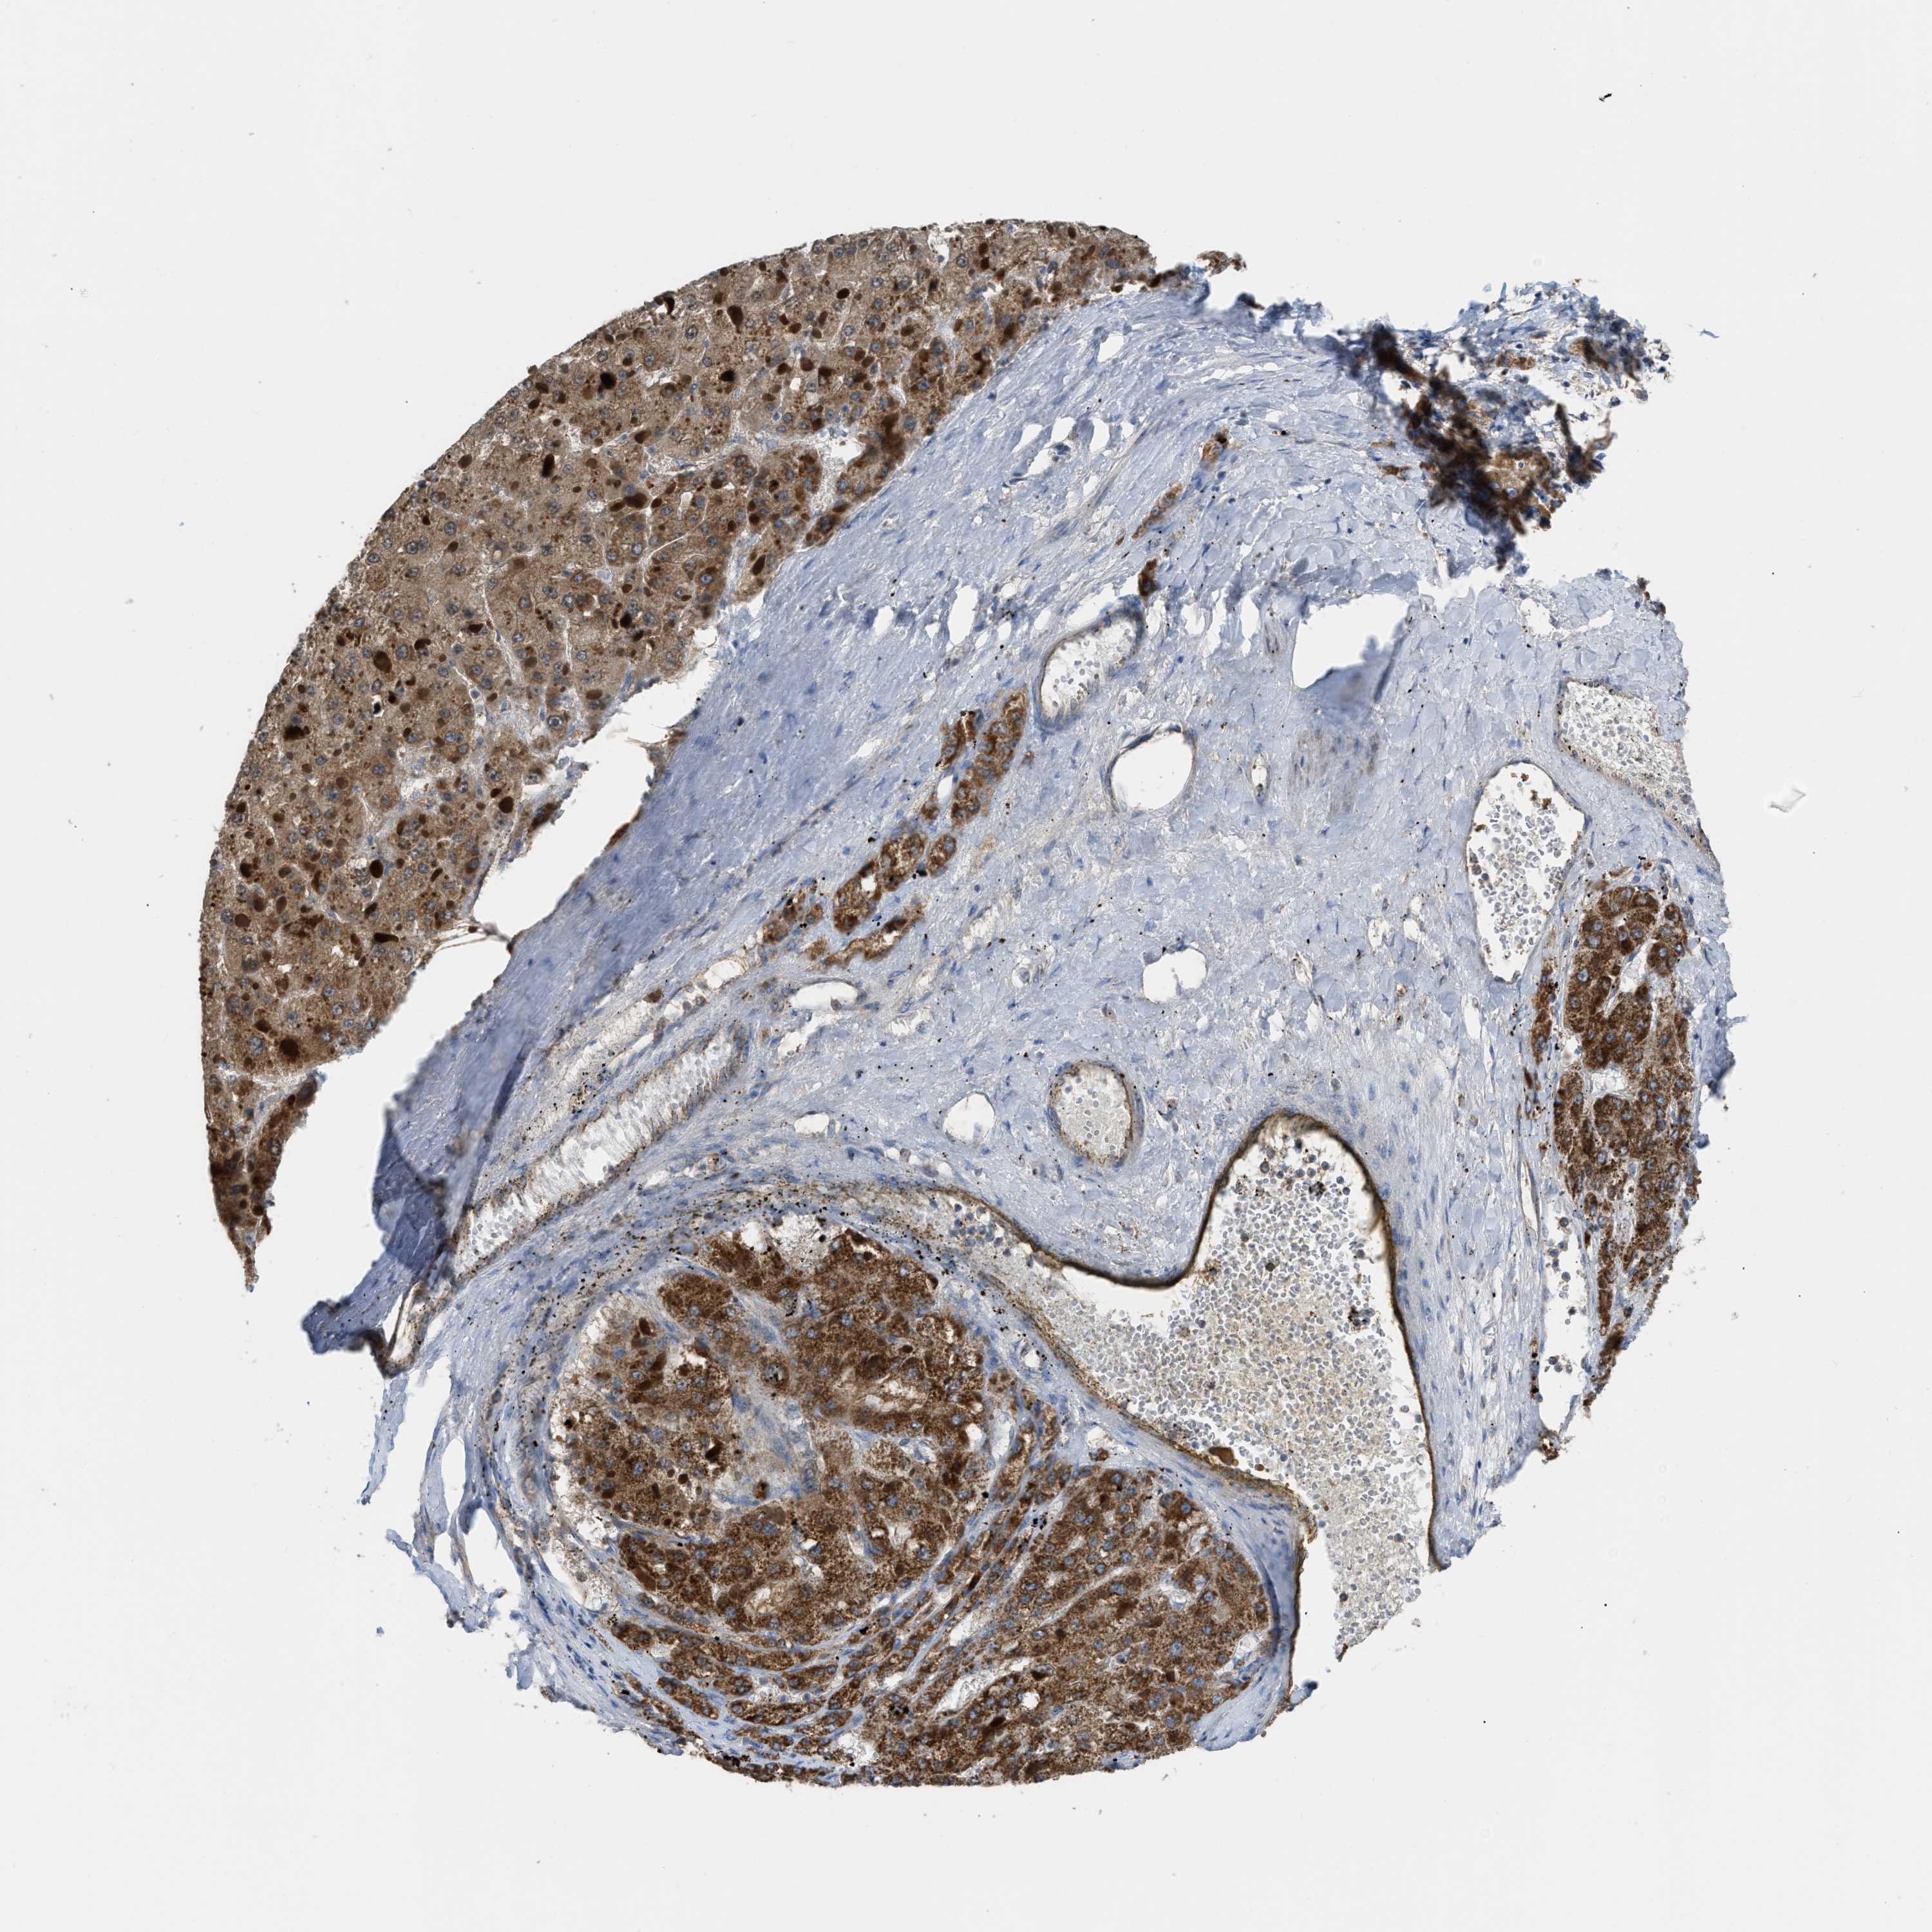

LIVER CANCER - Protein expressioni

A mouse-over function shows sample information and annotation data. Click on an image to view it in a full screen mode. Samples can be filtered based on level of antibody staining by selecting one or several of the following categories: high, medium, low and not detected. The assay and annotation is described here.

Note that samples used for immunohistochemistry by the Human Protein Atlas do not correspond to samples in the TCGA dataset.

Antibody stainingi

Antibody staining in the annotated cell types in the current human tissue is reported as not detected, low, medium, or high, based on conventional immunohistochemistry profiling in selected tissues. This score is based on the combination of the staining intensity and fraction of stained cells.

Each image is clickable and will lead to virtual microscopy that enables deeper exploration of all samples and also displays staining intensity scores, fraction scores and subcellular localization as well as patient and tissue information for each sample.

Antibody HPA018910

Antibody HPA018921

Antibody HPA018923

Staining

High

Medium

Low

Not detected

Intensity

Strong

Moderate

Weak

Negative

Quantity

>75%

75%-25%

<25%

None

Location

Nuclear

Cytoplasmic/membranous

Cytoplasmic/membranous,nuclear

Cholangiocarcinoma

Carcinoma, Hepatocellular, NOS